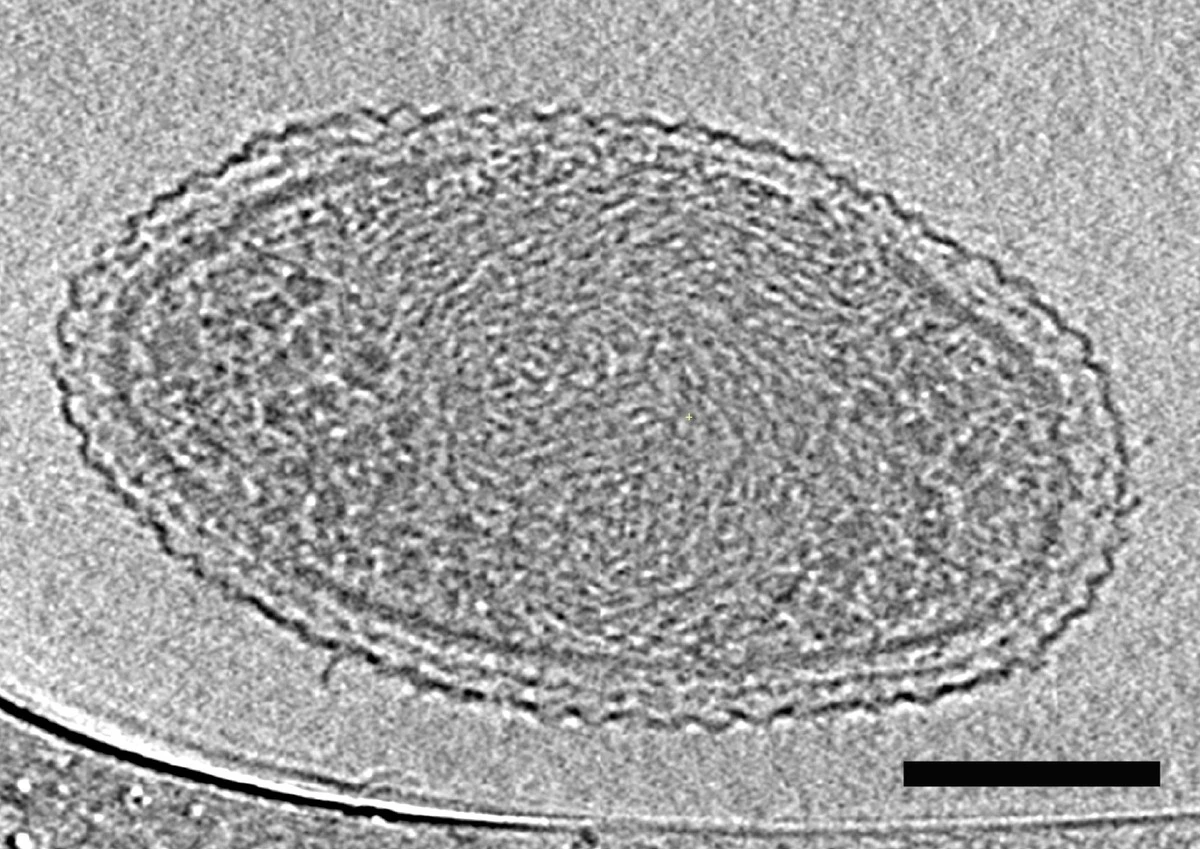

Bakterie nie są tylko biernym celem – to żywe organizmy, które potrafią adaptować się do stresu. Kiedy podajemy lek, bakterie nie poddają się bez walki. Zaczynają uwalniać mikroskopijne pęcherzyki, zwane BEV (bakteryjne pęcherzyki zewnątrzkomórkowe).

W moich badaniach przetestowałam, jak różne grupy antybiotyków wpływają na produkcję tych pęcherzyków. Wyniki były zaskakujące. Popularne leki z grupy beta-laktamów, które atakują ścianę komórkową bakterii, powodują, że patogeny uwalniają znacznie więcej szkodliwych pęcherzyków niż w przypadku innych metod leczenia.